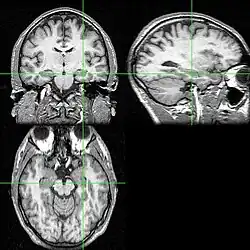

Neuroimágenes

Las pruebas de neuroimagen pueden identificar la causa de las crisis y el foco de las crisis, es decir, el lugar del cerebro donde comienzan las crisis.[5] En la epilepsia recién diagnosticada, la resonancia magnética (RM) puede detectar lesiones cerebrales en hasta el 12-14% de las personas con epilepsia.[31] Sin embargo, en las personas con epilepsia crónica, la RM puede detectar lesiones cerebrales en el 80% de las personas con epilepsia.[31] La RM de 3-Tesla se recomienda para aquellos con evidencia de epilepsia focal, como la epilepsia del lóbulo temporal.[5] Las anomalías identificadas mediante RM incluyen esclerosis hipocampal, displasia cortical focal, otras malformaciones cerebrales corticales del desarrollo, tumores del desarrollo y de bajo grado, hemangioma cavernoso, lesión cerebral encefalopatía hipóxico-isquémica, lesión cerebral traumática y encefalitis.[5]

La tomografía por emisión de positrones (PET) cerebral con 18F-fluorodeoxiglucosa (18F-FDG) puede mostrar una región cerebral de disminución del metabolismo de la glucosa en un momento entre convulsiones; esta región hipometabólica puede corresponder al foco convulsivo, y la PET es más sensible para la localización del foco convulsivo del lóbulo temporal en comparación con la epilepsia que surge de otros lóbulos cerebrales.[5] La tomografía computarizada de emisión monofotónica (SPECT) puede mostrar una región de disminución del flujo sanguíneo entre 40 y 60 segundos después de la inyección durante la crisis; esta región de flujo sanguíneo reducido puede corresponder al foco de la crisis.[5]

La tomografía computarizada (TC) es menos sensible que la RM para identificar tumores pequeños, malformaciones vasculares, malformaciones cerebrales del desarrollo cortical y anomalías en el lóbulo temporal medio.[31] La TC se aconseja en casos de urgencia cuando se sospecha que la causa de la epilepsia puede ser una hemorragia intracerebral, un absceso cerebral, un infarto cerebral de gran tamaño o un empiema subdural.[5][31] Una persona que necesite una neuroimagen pero no pueda someterse a una RM debido a la implantación de dispositivos como un marcapasos cardíaco, un desfibrilador o un implante coclear puede someterse a una TC. La TC puede demostrar mejor las anomalías cerebrales que contienen calcio y causan epilepsia, como en la esclerosis tuberosa y el síndrome de Sturge-Weber.[5][31]